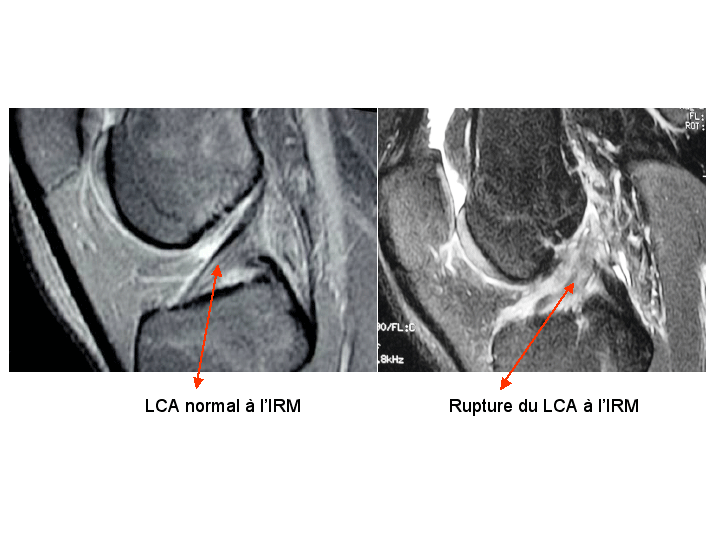

Le diagnostic est le plus souvent clinique. L’IRM est très fiable pour apprécier la rupture des ligaments et les lésions méniscales. L’IRM permet également d’objectiver les contusions osseuses (bone bruise) qui sont responsables des douleurs persistantes post-traumatiques.